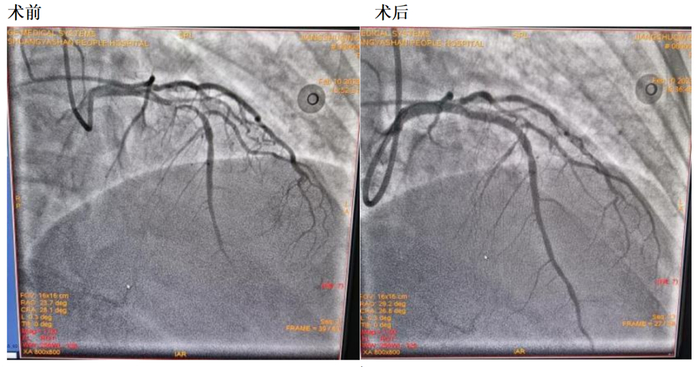

心血管造影(2023年02月10日):右桡动脉、右肱动脉走行未见异常。冠脉分布呈现右优势型。左右冠开口位置无异常。左主干内膜光滑无有意义狭窄,前降支斑块浸润,前降支近段最狭窄90%,回旋支斑块浸润,无有意义狭窄,右冠脉斑块浸润,无有意义狭窄。

入院诊疗方案:入院后给予硝酸异山梨酯扩血管、那屈肝素钙抗凝、阿司匹林及替格瑞洛抗血小板聚集、瑞舒伐他汀钙调脂稳定斑块、美托洛尔降低心肌耗氧量等对症治疗。行冠脉造影检查示:前降支近段最狭窄90%,于前降支近段植入支架1枚。术后在常规药物治疗的基础上增加悦康®活心丸(浓缩丸)每次2粒,每日3次治疗,患者症状明显改善,未再诉胸痛,症状好转出院。